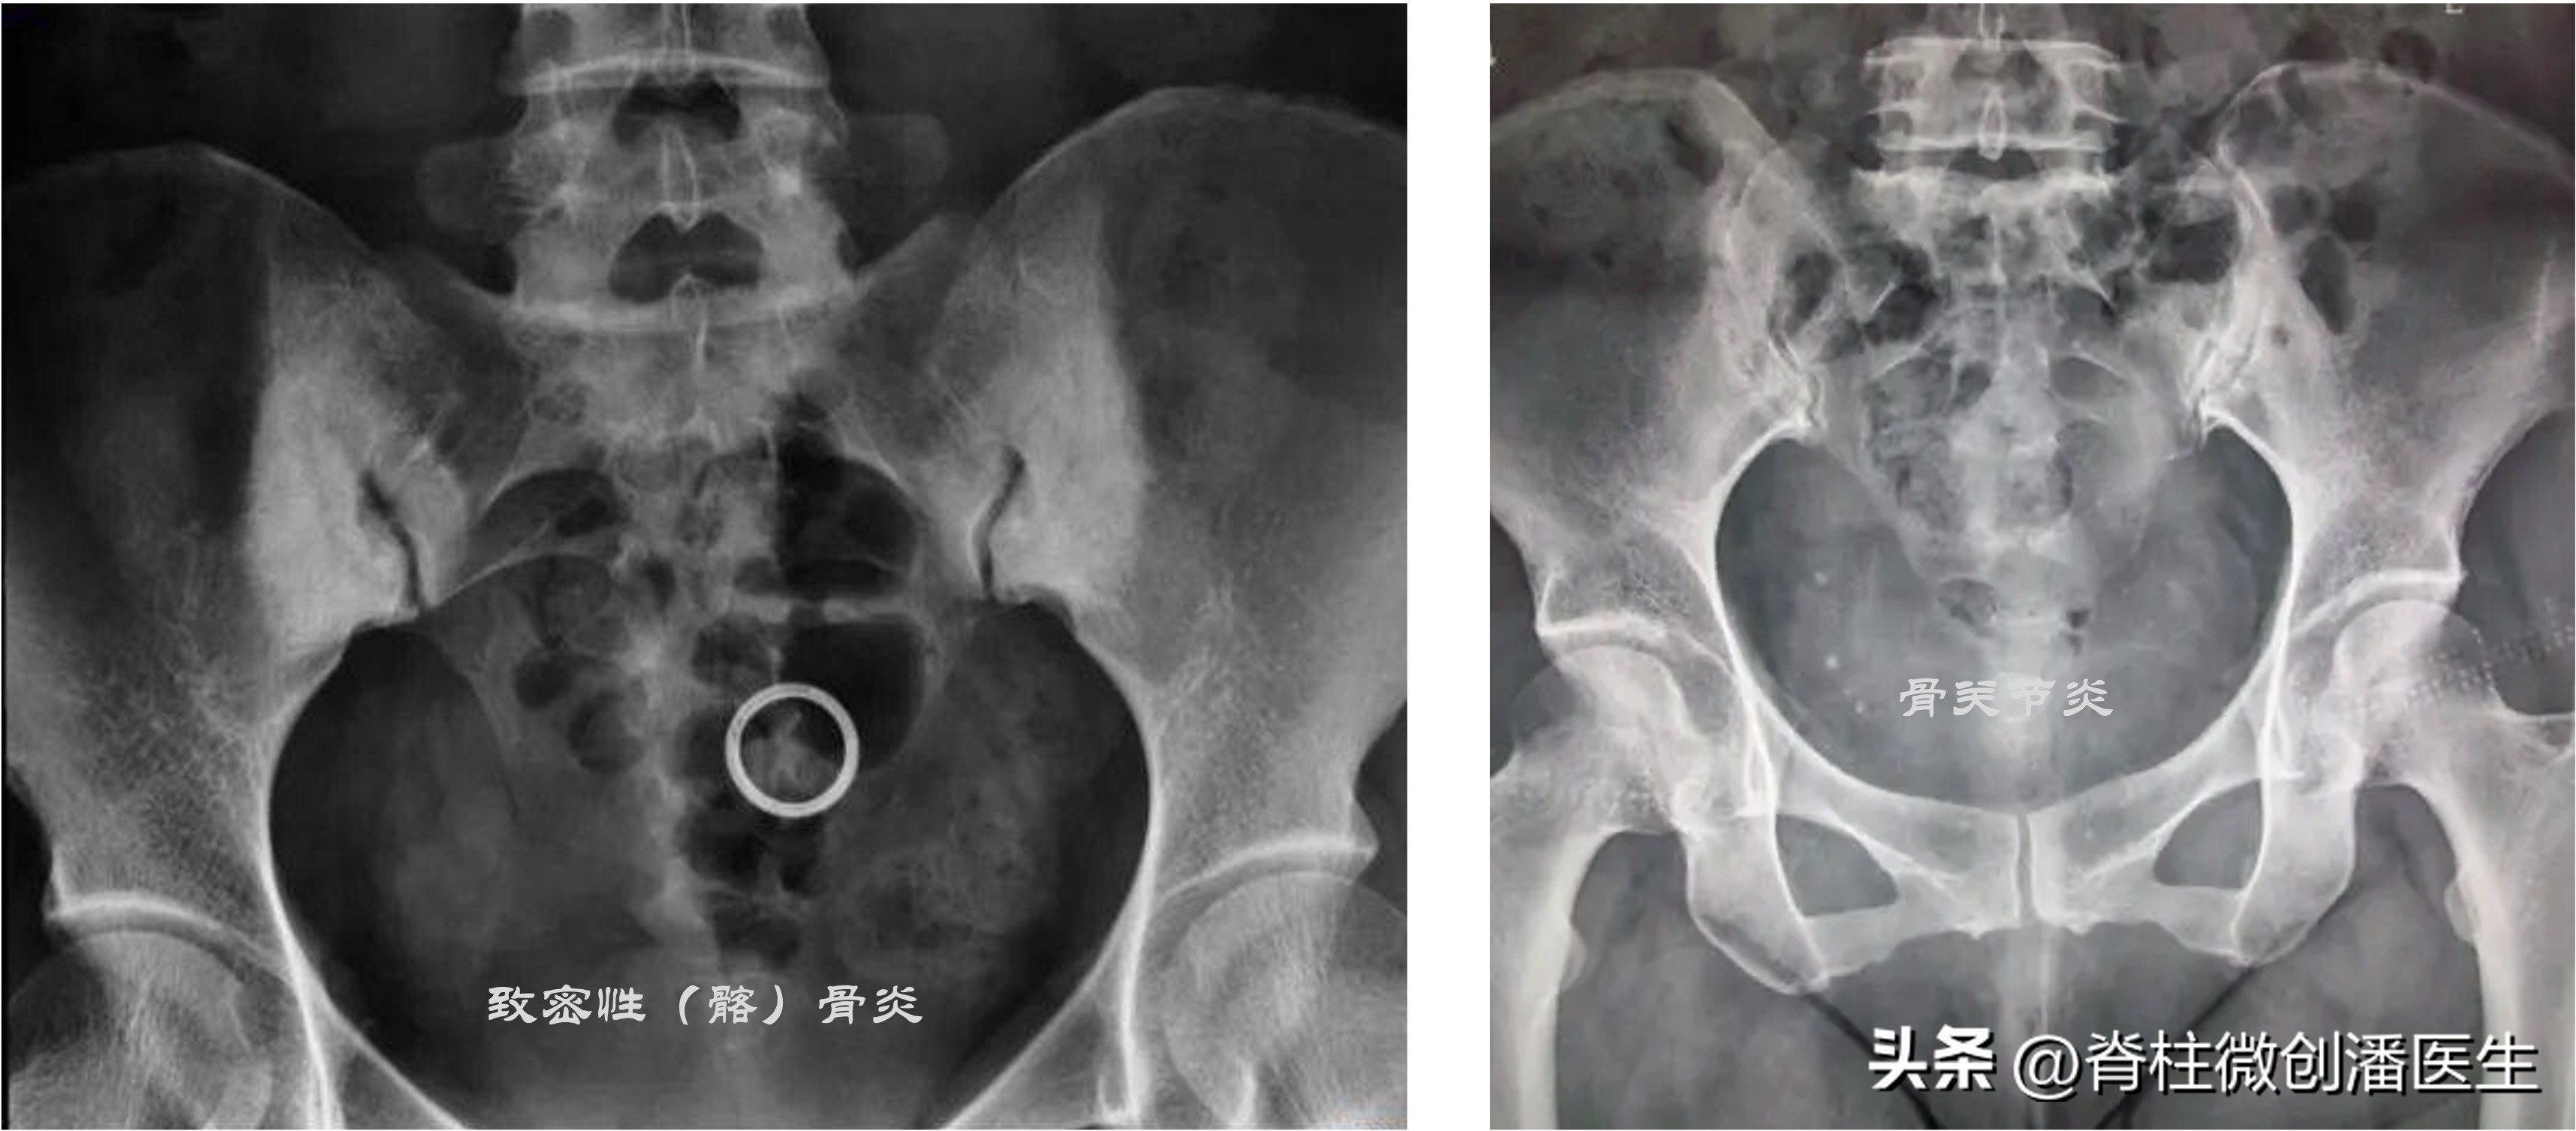

二、 骶髂关节炎症:骶髂关节单纯性化脓性炎症较少见,但强直性脊柱炎、类风湿性关节炎却常见。骶髂关节结核也是常见的结核感染部位。此外,还有Reiter综合征、慢性溃疡性结肠炎、牛皮癣性关节炎等。致密性(髂)骨炎也被认为与骶髂关节疼痛有关,其在骶髂关节的髂骨处发现局限性硬化区,不侵犯骶髂关节,多见于妇女。

三、 骶髂关节退变(骶髂关节骨关节炎):据估计55岁以上人群约67%有骶髂关节的退变,但主要是创伤后失稳退变引起。其特点是骶髂关节的下部疼痛及压痛,耻骨联合处也有压痛,这是因为骨盆环的某一处损伤必然涉及其他部位。骶髂关节牵张试验阳性;行走时患侧臀部下垂性跛行(Trendelenburg 征)。X片可见骶髂关节下部呈增生性改变,双侧可不对称性,关节面软骨下骨硬化,关节下端骨质增生,骨赘形成,或同时有小的囊性变,多伴有不同程度的脊柱退变。

当病人主诉骶髂关节部位疼痛,经检查疼痛的根源主要是在骶髂关节时,应投照骨盆正位片,必要时可投照骶髂关节的专用体位片,即患者坐在X片盒上,身体略前倾,X线球管自后上方对准健侧的骼后上棘,使其与患侧骶髂关节呈45°角摄片,可较清晰地显示骶髂关节面。或 直接选择更为直观的骶髂关节CT检查。

骶髂关节的X片或CT除可协助确定上述骶髂关节病变外,还可同时确定一些侵犯骶髂关节的其他疾病:①骶髂关节松弛:多见于经产妇,骶髂关节间隙增宽,可伴有退行性变,同时耻骨联合处也可退变。松弛明显者,单足站立位时投照,可见持重侧耻骨上移。②骶髂关节结核:常为单侧,且多侵犯关节的下部,关节边缘出现虫蚀样病灶,以后关节破坏,间隙增宽并可有死骨形成,可伴有寒性脓肿。③ 强直性脊柱炎:双侧骶髂关节受侵,初期关节间隙模糊,逐渐出现串珠样改变,最后关节硬化、间隙消失。④Reiter综合征:骶髂关节面破坏,周围骨质硬化明显,临床上伴有尿道炎、结膜炎等症状。